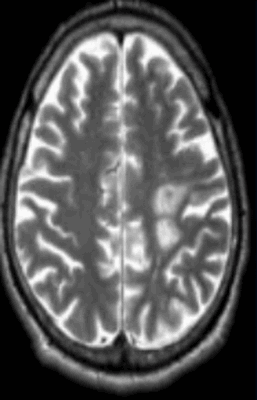

![Очаг демиелинизации на МРТ]()

Очаг демиелинизации на МРТ